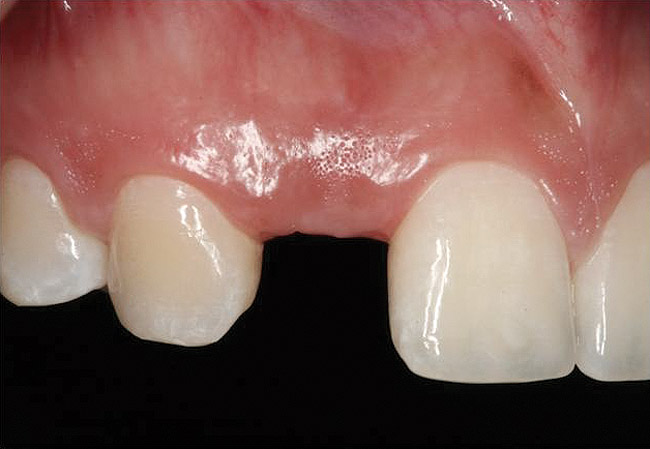

Figure 21   Gingival zenith planning: The location of the gingival zenith for this missing lateral incisor is not fully evident during initial clinical evaluation (Fig 21). Subsequent diagnostic waxing reveals the position of the planned gingival zenith (Fig 22). A thermoplastic template captures the position of the zenith and enables transferring this location to the clinical environment (Fig 23 and Fig 24). Final crown contours are defined by soft-tissue form (Fig 25).

Figure 21

Figure 22  Gingival zenith planning: The location of the gingival zenith for this missing lateral incisor is not fully evident during initial clinical evaluation (Fig 21). Subsequent diagnostic waxing reveals the position of the planned gingival zenith (Fig 22). A thermoplastic template captures the position of the zenith and enables transferring this location to the clinical environment (Fig 23 and Fig 24). Final crown contours are defined by soft-tissue form (Fig 25).

Figure 22